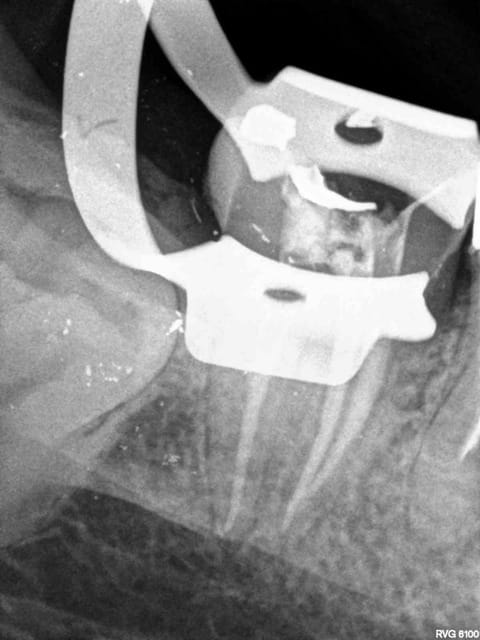

17/11/2014 à 18h23

Capteur kodak 6100, Angulateur kodak, on ne dépose rien du tout.

1 rmn1sd - Eugenol

2 xuaeeq - Eugenol